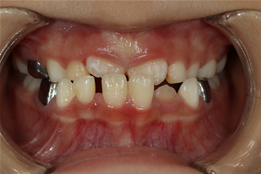

앞니가 비뚤게 나서 교정하러 온 친구입니다.

입천장의 고정식 확장장치를 이용해 좌우로 벌려서 치아를 배열할 공간을 만들었습니다.

그런데 친구가 학교에서 부딪혀서 다쳐 왔습니다.

바로 처치(치아를 철사로 부목 고정)후 신경치료를 진행하였습니다.

이후 치아배열을 마무리하여 가지런한 이를 가지게 되었습니다.